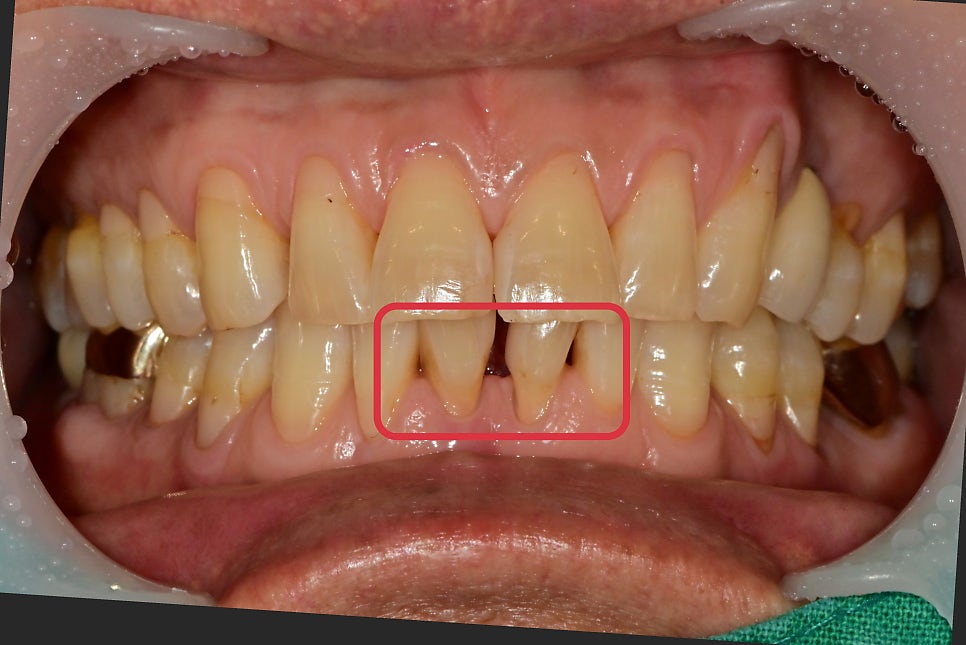

아래 앞니 쪽이 잇몸이 자주 붓는다고

내원해 주셨습니다.

2개의 치아가 치주염으로 인한 치조골 소실로

치아 이동이 일어나 공간이 벌어져있었습니다.

2개의 치아 중 한 개는 치주염이 상당히 많이 진행되어 있었고, 그 옆 치아도 2도 이상의 동요도가 관찰되어 2개의 치아가 발치가 필요했습니다.